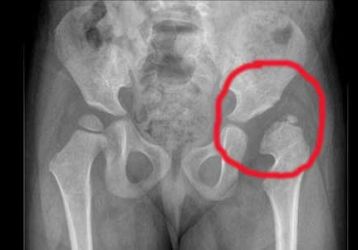

• Дисплазия. Для болезни характерно неправильное развитие сочленения. При нем головка кости бедра выпадает из вертлужной впадины.